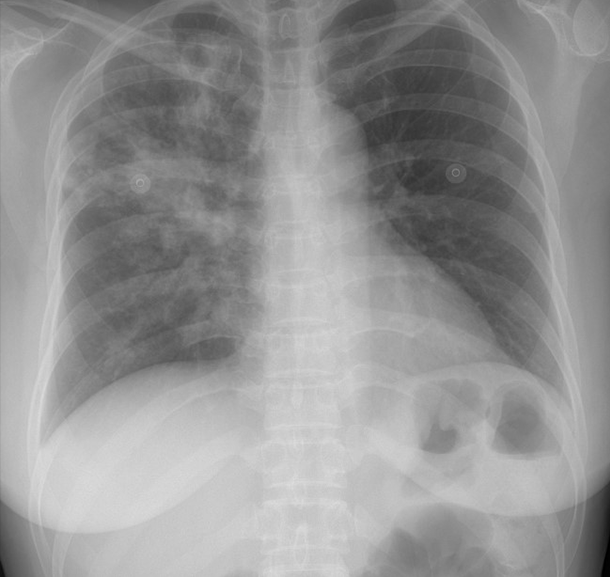

활동성 폐결핵과 비결핵성항산균 폐질환의 진단은 어떻게 하는지요?

환자의 임상 증상 문진과 진찰 후, 흉부 X선 검사 및 흉부 CT가 진단에 도움이 됩니다.

그림: 폐결핵과 비결핵성항산균 폐질환의 흉부엑스레이 사진과 흉부전산화단층활영 사진

비결핵성항산균 폐질환은 폐결핵과 비교하였을 때 서서히 진행하거나 변하지 않을 수 있으며, 만성적인 경과를 보이고, 진단이 늦어지는 경향이 있습니다. 두 질환은 모두 환자의 객담을 통한 객담 항산균 도말검사, 객담 항산균 배양 검사를 진행합니다. 객담 배양이 되기 전에는 객담 도말 검사 양성 소견만으로는 결핵균과 비결핵성항산균이 구별이 되지 않으며, 구별을 위해서 결핵균 핵산증폭검사(TB-PCR) 검사를 시행합니다.